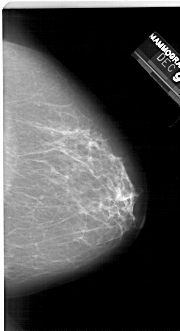

A_1245_1.RIGHT_MLO

RIGHT_MLO LINES 6661 PIXELS_PER_LINE 3706 BITS_PER_PIXEL 12 RESOLUTION 43.5 NON_OVERLAY